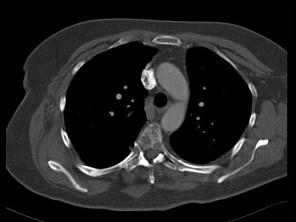

问题 女,47岁,背痛半月余,2个月前被诊断为乳腺癌肝转移,请结合影像学检查,选出最可能的诊断 ( )

选项 A、椎体压缩骨折 B、脊椎退行性变 C、脊椎转移瘤 D、化脓性脊柱炎 E、脊椎结核

答案 C